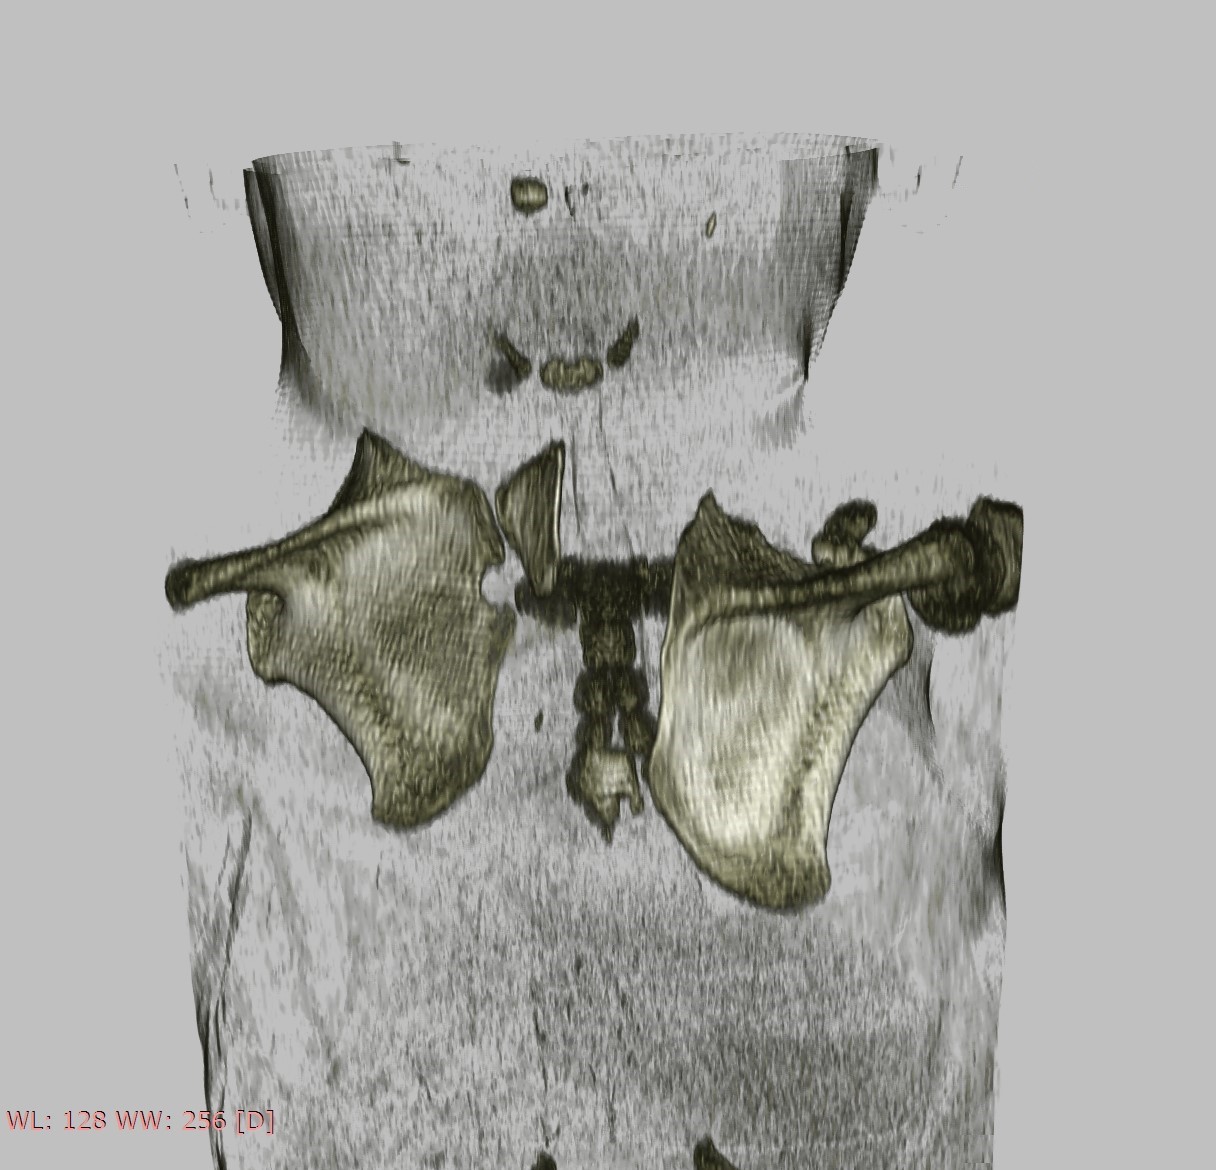

Subsequent radiographs and an ultrasound of both shoulders and scapulae and a close-up X-ray of the left shoulder revealed a fusion of costa 3 and 4. For further evaluation of the cervical spine we made a CT scan which showed a partial fusion of the vertebral corpus C5-C7 on the left and corpus Th2-Th3, Th5-Th6, a fork rib of the 4th rib on the right side (figure 2) and a different morphology of costa 7 on the right. Also seen was a bilateral Sprengel’s deformity; left grade 3 with os omovertebrale, right grade 2 (table 1), articulating with the spinous process C7 (figure 3). As a result of these findings the parents were informed about the diagnoses and the patient will be monitored by a paediatric orthopaedic surgeon until adulthood. Physiotherapy was continued with the aim of maintaining shoulder function. Clinical genetic research revealed no known associated gene mutations, but did show a sequence change in the GDF6 gene with unknown clinical consequences.

Figure 3. Os omovertebrale right, grade 2 articulating with C7 processus spinosus, bilateral Sprengel’s deformity.